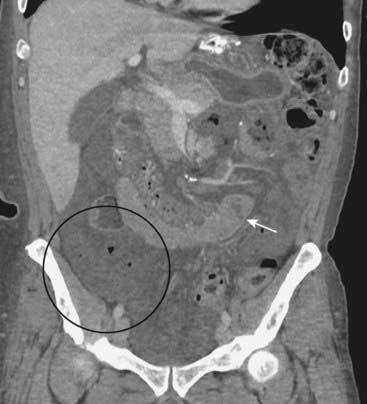

Figure 14-3 Small bowel obstruction from inguinal hernia.

A, The scout image from a CT scan of the abdomen reveals dilated loops of small bowel (solid black arrow) caused by a left inguinal hernia (white circle). Loops of bowel should normally not be present in the scrotum. B, Coronal-reformatted CT scan on another patient shows multiple fluid-filled and dilated loops of small bowel (solid white arrows) from a right inguinal hernia (white circle) containing another dilated loop of small bowel (dotted white arrow).